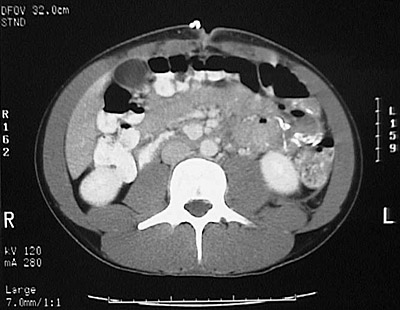

[L3] This is a normal abdominal CT scan with contrast demonstrating the liver and gallbladder and transverse colon and small intestine and lower pole of right kidney and lower pole of left kidney and aorta and inferior vena cava and psoas muscle and in the abdomen.